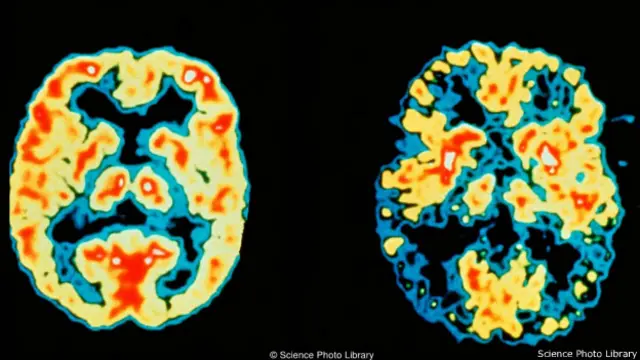

इमेज स्रोत, Science Photo Library

बढ़ती उम्र के साथ कमज़ोर होती याददाश्त पर भी बहुत से रिसर्च किए गए हैं.

ये पाया गया कि जो लोग अपनी नींद के साथ नाइंसाफ़ी करते हैं उनकी याददाश्त जल्दी कमज़ोर होती है.

दरअसल जब हम सो जाते हैं तब हमारा दिमाग जमा की गई बातों में कांट छांट करता है.

जो बातें काफ़ी पुरानी हो जाती हैं उन्हें साफ़ करके दिमाग की स्टोरेज मेमरी में जगह बनाता है.